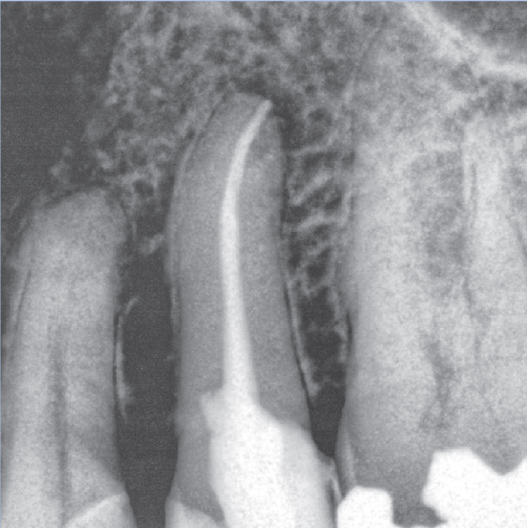

Before

After

Before Root Canal treatment

After Root Canal treatment